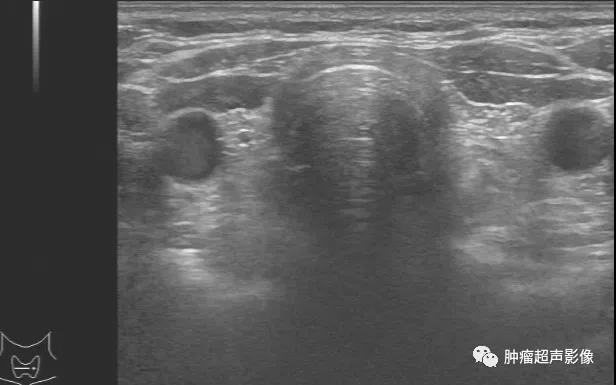

异位甲状腺(ETG)是指在正常甲状腺位置以外出现的甲状腺组织。异位甲状腺属于甲状腺胚胎发育异常或错构的甲状腺组织发育而成,在下降的过程中受阻,甲状腺就不能在正常位...